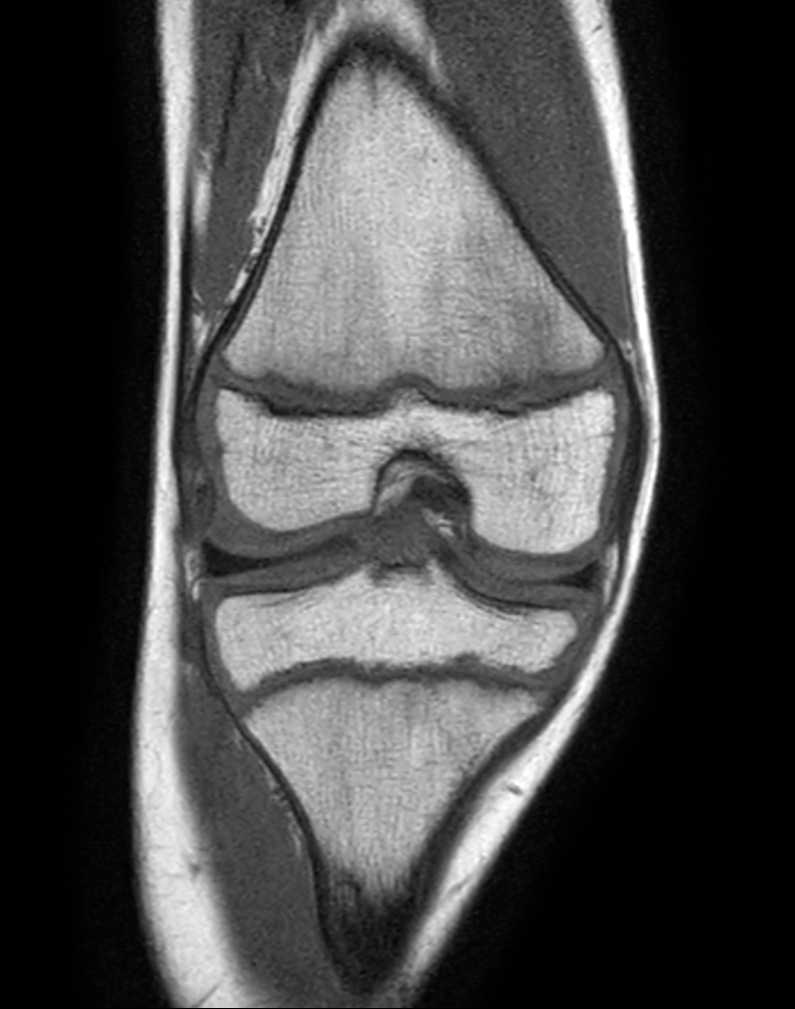

Coronal T1w TSE